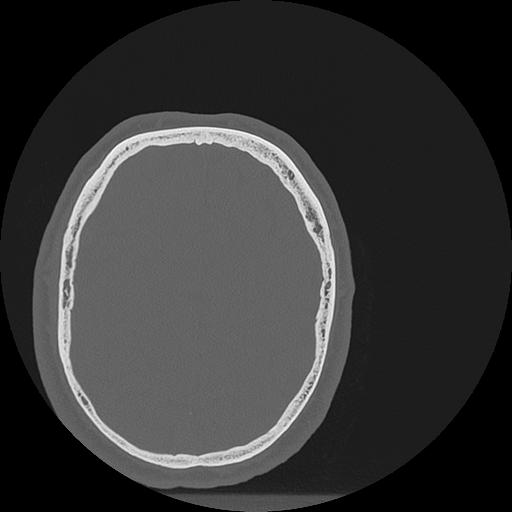

7 HUESO,,Vol,0.5,HUESO,,